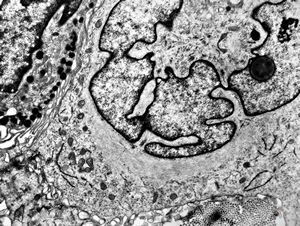

F, 37y. | mycosis fungoides … cerebriform nucleus of Sézary cell